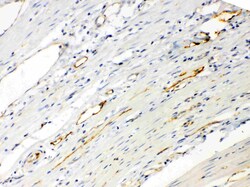

Reconstitute with 0.2 mL of distilled water to yield a concentration of 500 μg/mL. Positive Control - WB: rat stomach tissue, mouse ovary tissue. IHC: mouse intestine tissue, rat intestine tissue, rat cardiac muscle tissue, human intetsinal cancer tissue.

| Immunohistochemistry (Paraffin), Western Blot | |